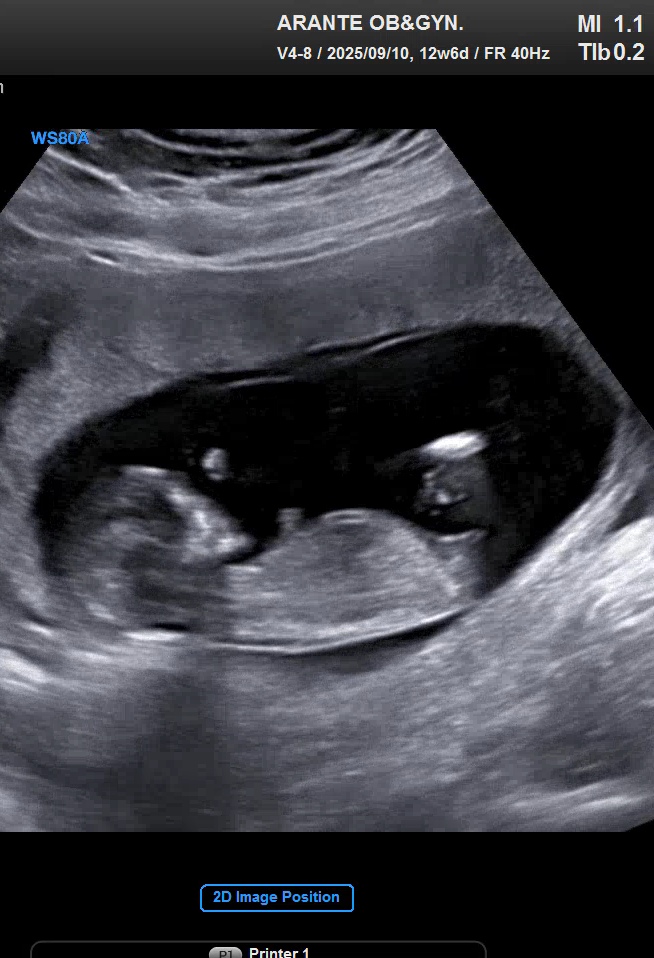

12주6일이에요! 각도법 봐주실분~♡